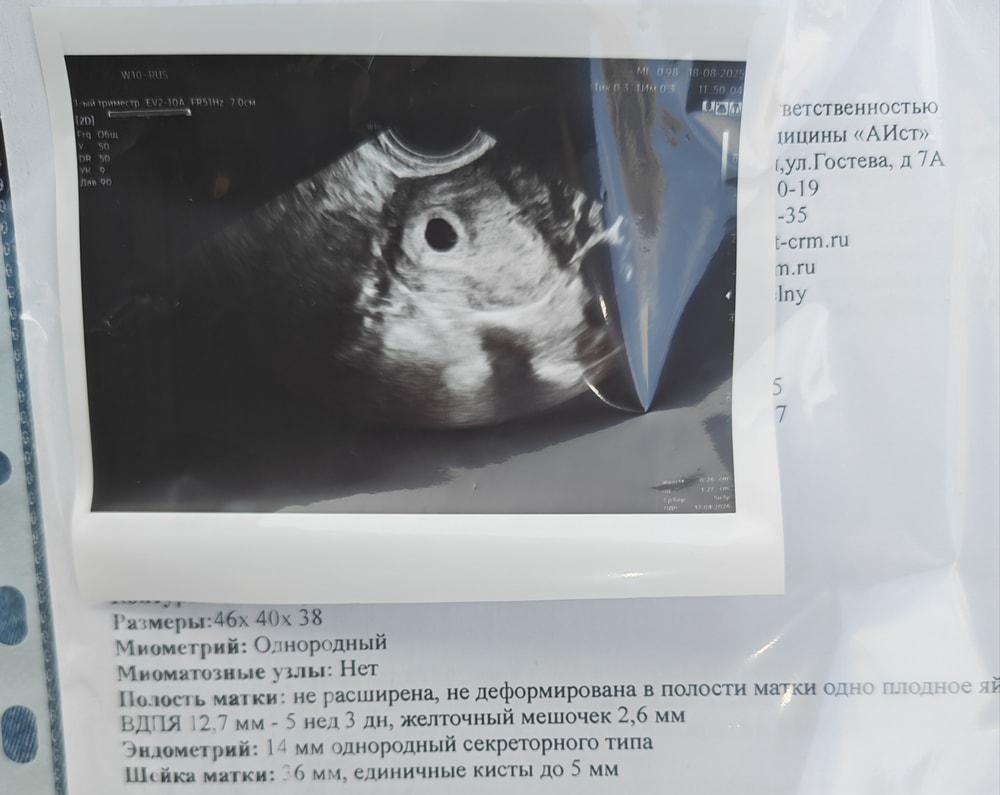

Результаты УЗИСделали сегодня первое УЗИ.

Срок по м: 5+1

Срок по размерам пя: 5+3 ❤

Желточный мешочек на месте)